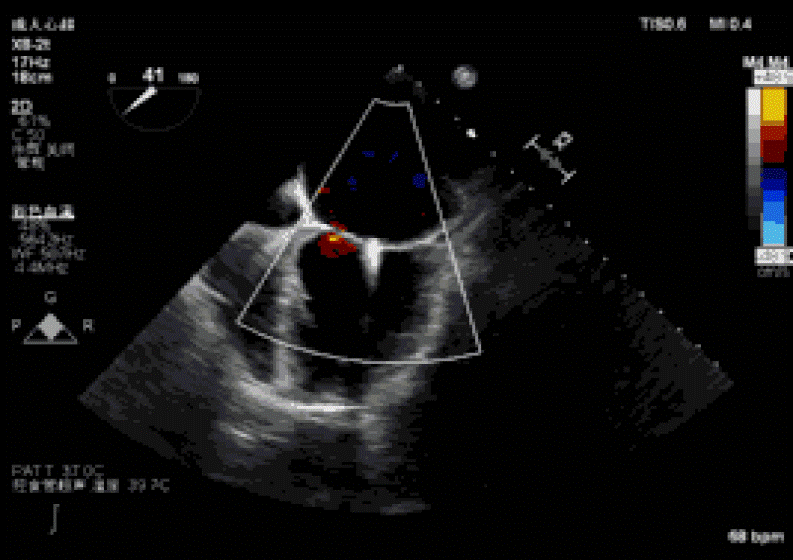

2019年3月5日中午,復旦大學附屬中山醫(yī)院葛均波院士團隊的周達新教授、潘文志副主任醫(yī)師,心外科的魏來教授、楊曄主治醫(yī)師,心超室的潘翠珍教授、李偉主治醫(yī)師,麻醉科的郭克芳教授,使用最新一代心臟超聲機器Philips EPIQ 7C,完成一例經(jīng)心尖二尖瓣夾合術。新一代超聲機器分辨率高,圖像處理速度快,圖像界面舒適,使得手術非常順利。導管操作時間(從穿刺心尖到閉合心尖時間)僅10分鐘?;颊咝g后即刻效果滿意,反流從重度減少到輕微。本例是國內(nèi)首例使用最新一代心超機器Philips EPIQ 7C的X8-2t食道探頭進行術中經(jīng)食道超聲,采用TrueVue心腔鏡成像技術指導心臟介入手術,獲得滿意的結果。